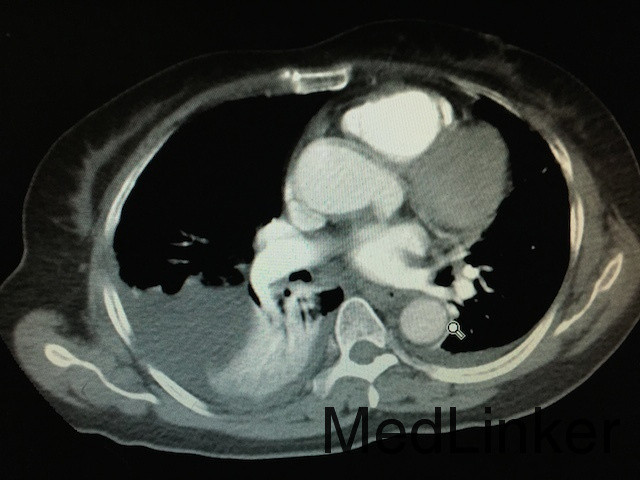

随访:患者病情稳定后行胸部CTA如下图:双肺动脉分支栓塞,双肺片状影,双肺下叶局部膨胀不全,双侧胸腔积液。转至ICU后,患者生命体征稳定,暂不考虑行溶栓治疗,予以低分子肝素继续抗凝治疗,复查ECG后示:Q波深度较浅减低,T波恢复正常,抗凝有效。 讨论:患者为PCNL术后,由于手术时间长,且术中由于行结石位,下肢长时间受压,加上患者年龄大,很容易形成深静脉血栓,患者下地导致血栓脱落,阻塞肺部血管,造成肺动脉栓塞。